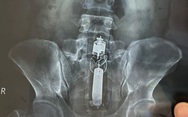

Nam bệnh nhân nhập viện cấp cứu vì kẹt đồ chơi tình dục trong trực tràng

TTO - Bệnh viện Quân y 175 TP.HCM cho biết vừa nội soi lấy dị vật là đồ chơi tình dục cho một bệnh nhân nam do trong quá trình sử dụng đã để 'đồ chơi' trôi xuống trực tràng.